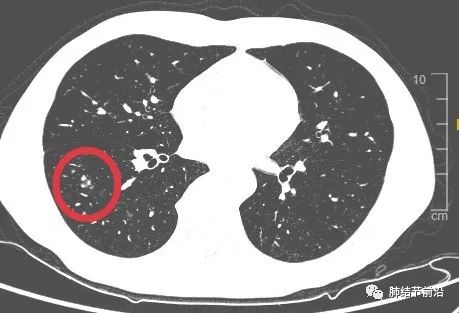

磨玻璃变实性,患者很担心。但是从这个结节的发展过程,基本可以排除恶性。告知患者不用紧张。

另外,CT显示为靠近胸膜,斑斑点点的相邻病灶,不符合结核卫星灶,符合隐球菌感染表现。

肿瘤性磨玻璃结节生长缓慢,基本不可能三个月变实性。因此本例从病程上,即可判断为炎症性,这个情况不要着急手术。后续根据CT影像特点,给予相应血液检查得以确诊。